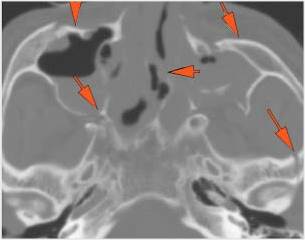

The mesial naso-orbito-ethmoid complex is fractured. Specifically, there is bony injury of the nasal bones or the frontal process of the maxilla and the medial walls of the orbit are abnormal. |

Yes | NA |

The nasolacrimal canal is fractured. |

There is injury of the ethmoid complex. Specifically, the ethmoid roof, olfactory fossa and the cribriform plate are fractured and/or significantly dehiscent. |

The frontal bone and frontal sinus inner and outer tables are fractured. |

The the zygomatic arch, frontozygomatic suture or infraorbital rim are fractured. |

The lateral wall of the orbit is fractured. |

LeFort type III, orbital zygomatic and orbital floor and fronto - naso-ethmoidal complex fractures with possible injury optic nerve/sheath - extent described above.